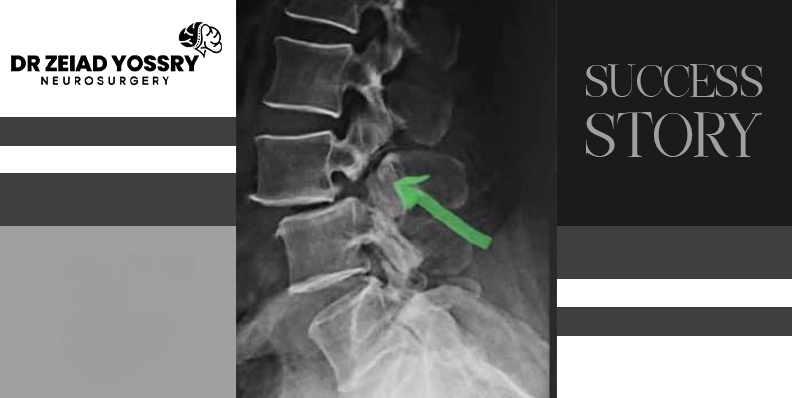

The patient went to consult Dr. Zeiad Yossry, who performed a physical and neurological examination. The examination included examining her back and palpating the painful area. Reduced reflexes were also found in the knee and ankle. The patient underwent several tests and imaging scans, including an MRI of her lumbar vertebrae. After reviewing the tests and a thorough examination, Dr. Zeiad Yossry informed her that she had a herniated disc and a fracture in her lumbar vertebrae, which required urgent intervention.

Intervertebral discs are protective, shock-absorbing cushions between the vertebrae of the spine. When a disc bulges, herniates, or ruptures, it can allow the inner, jelly-like portion of the disc to protrude into the surrounding tissue. This protruding portion can compress the spinal cord or a nearby nerve, causing pain, numbness, or weakness either around the damaged disc or anywhere along the area supplied by that nerve. A lumbar vertebral fracture caused damage to the spinal cord, preventing the patient from moving and walking. The earlier the intervention is initiated in such cases, the greater the chance of avoiding permanent spinal cord damage.